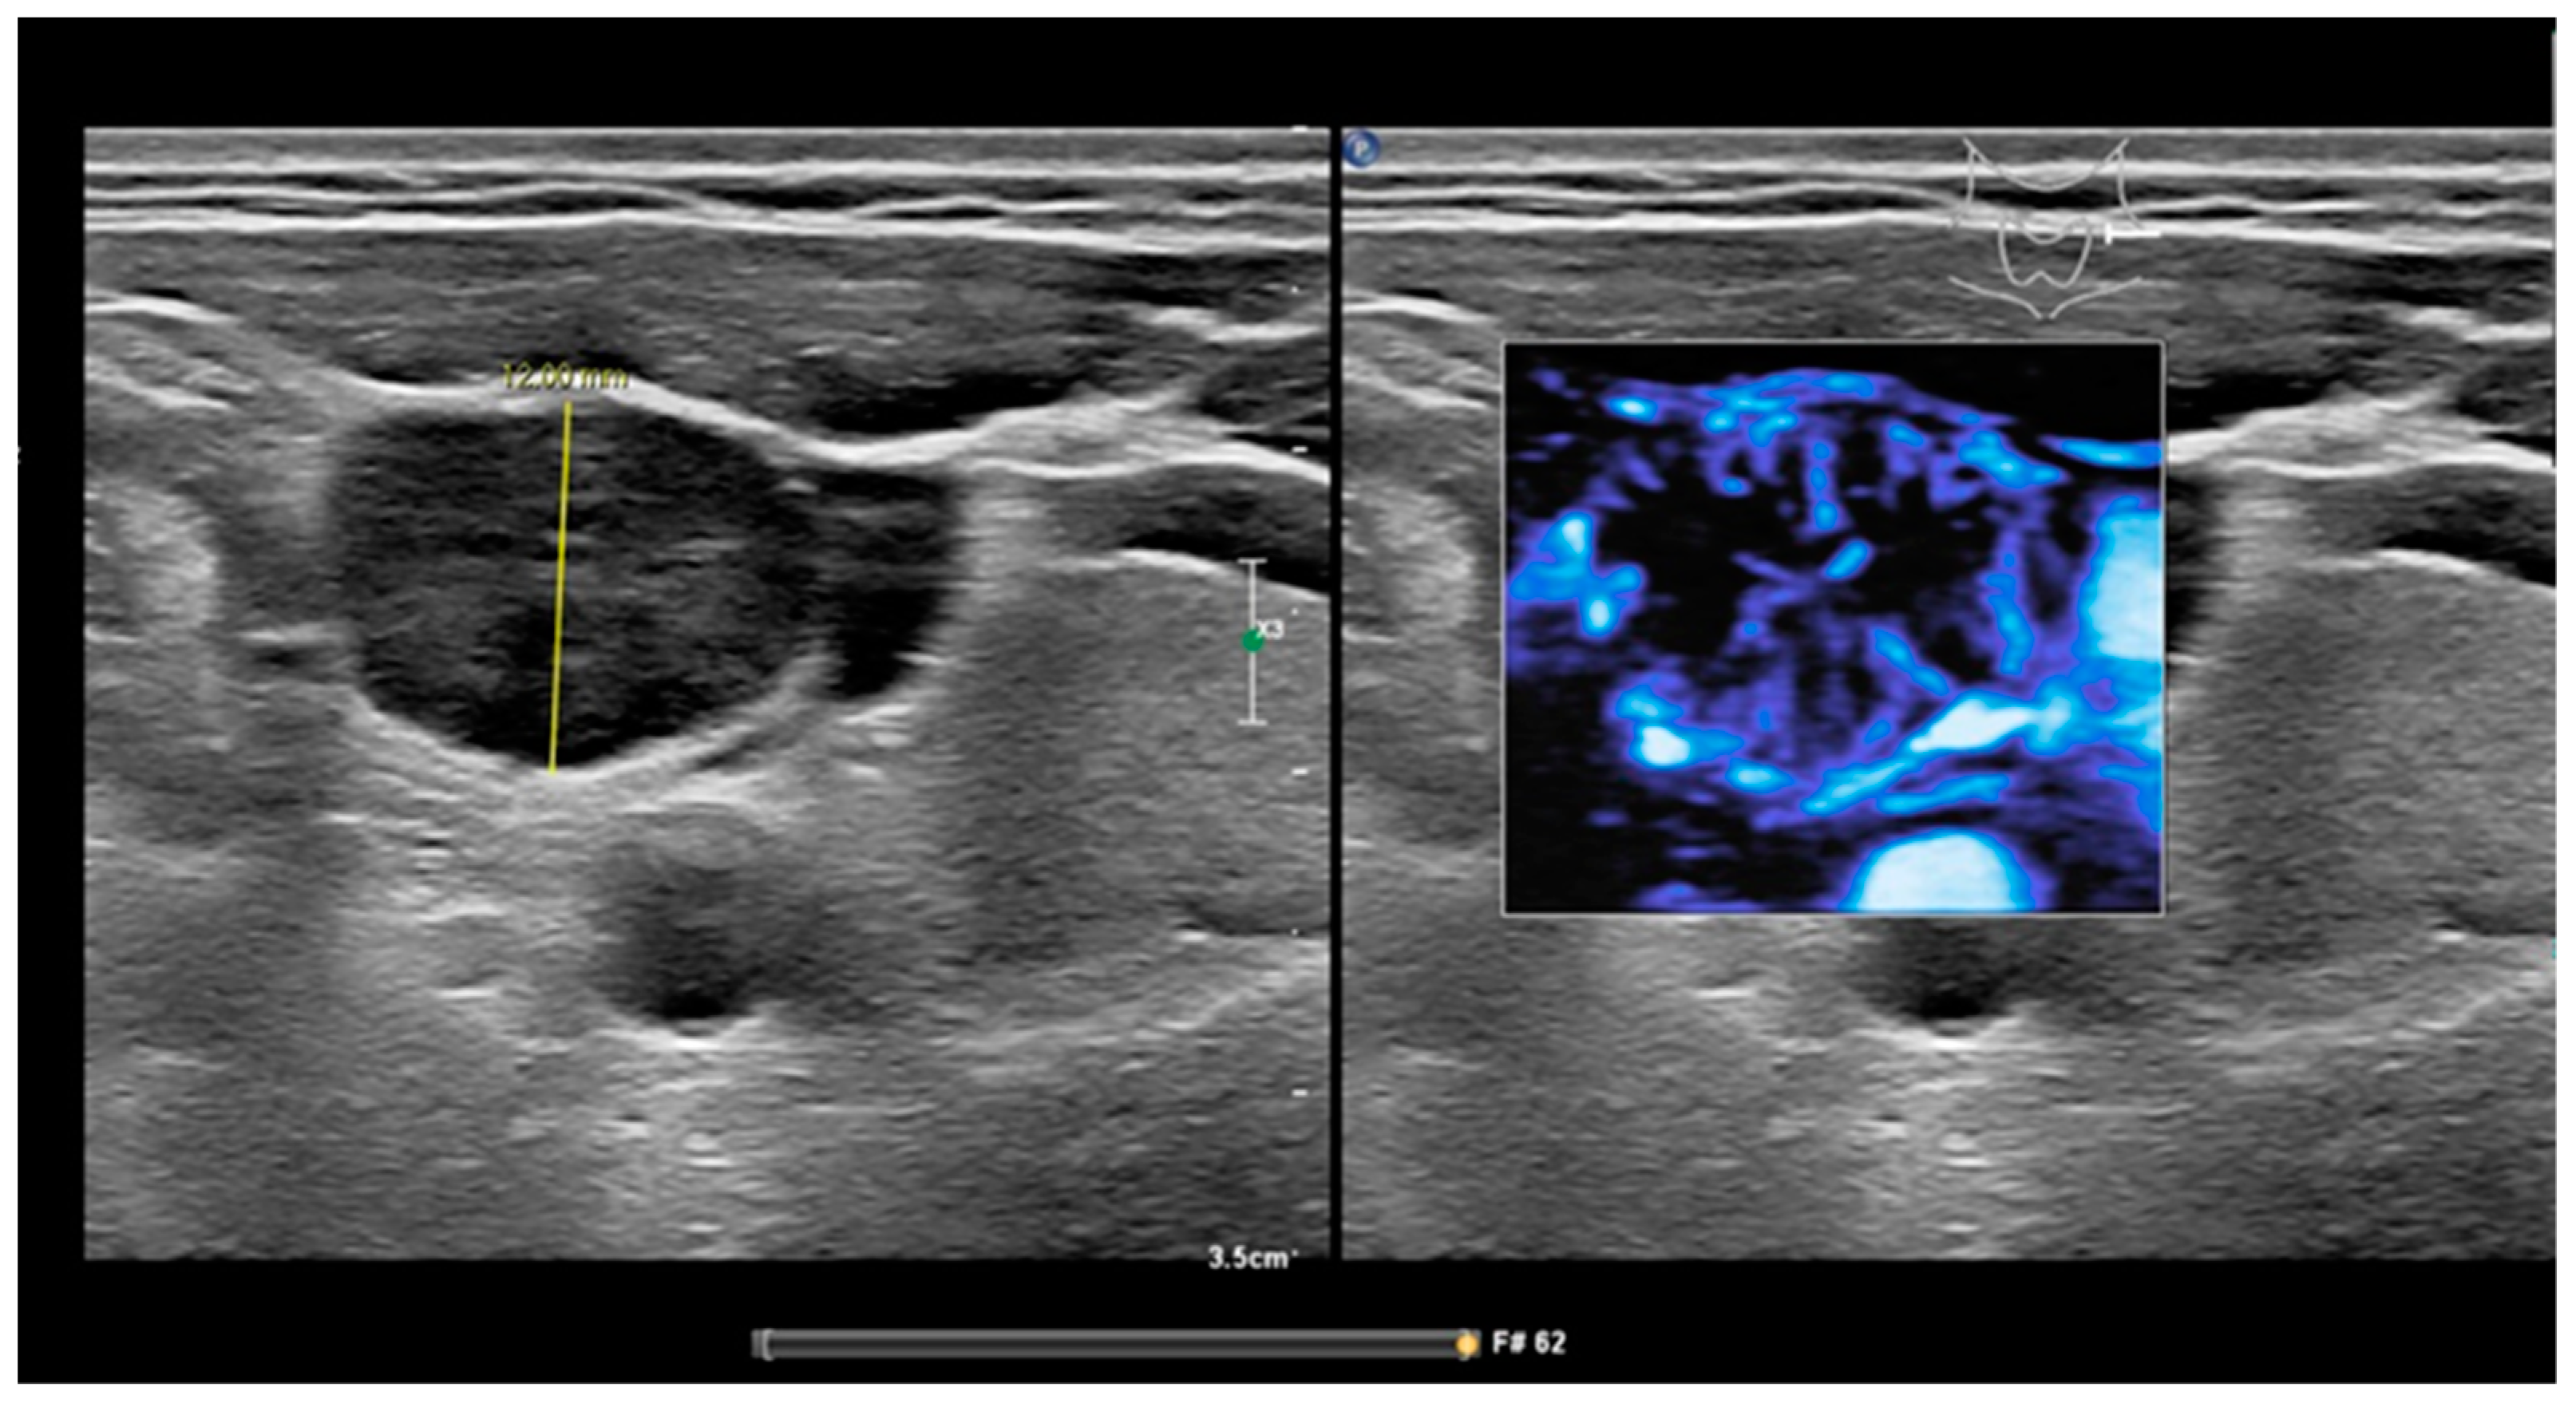

3.1.4. Peripheral Vascularization

3.1.5. Absent Hilum Sign